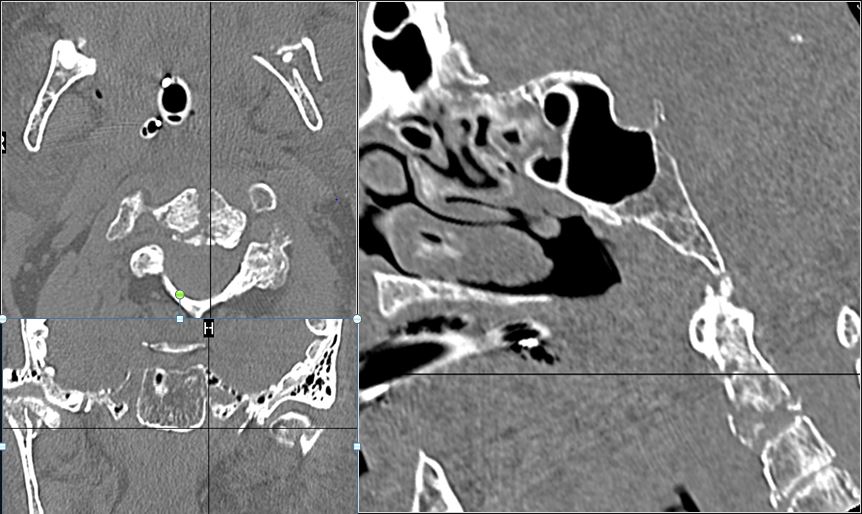

Mandible and Temporomandibular Joints

There is bony injury or displacement of the body, angle, ramus, parasymphyseal region, alveolar ridge, and condylar and coronoid process of the mandible. [In case of fracture, describe complexity and displacement].

Cervical Spine

The visualized portions of the cervical spine are abnormal for the patient’s age.